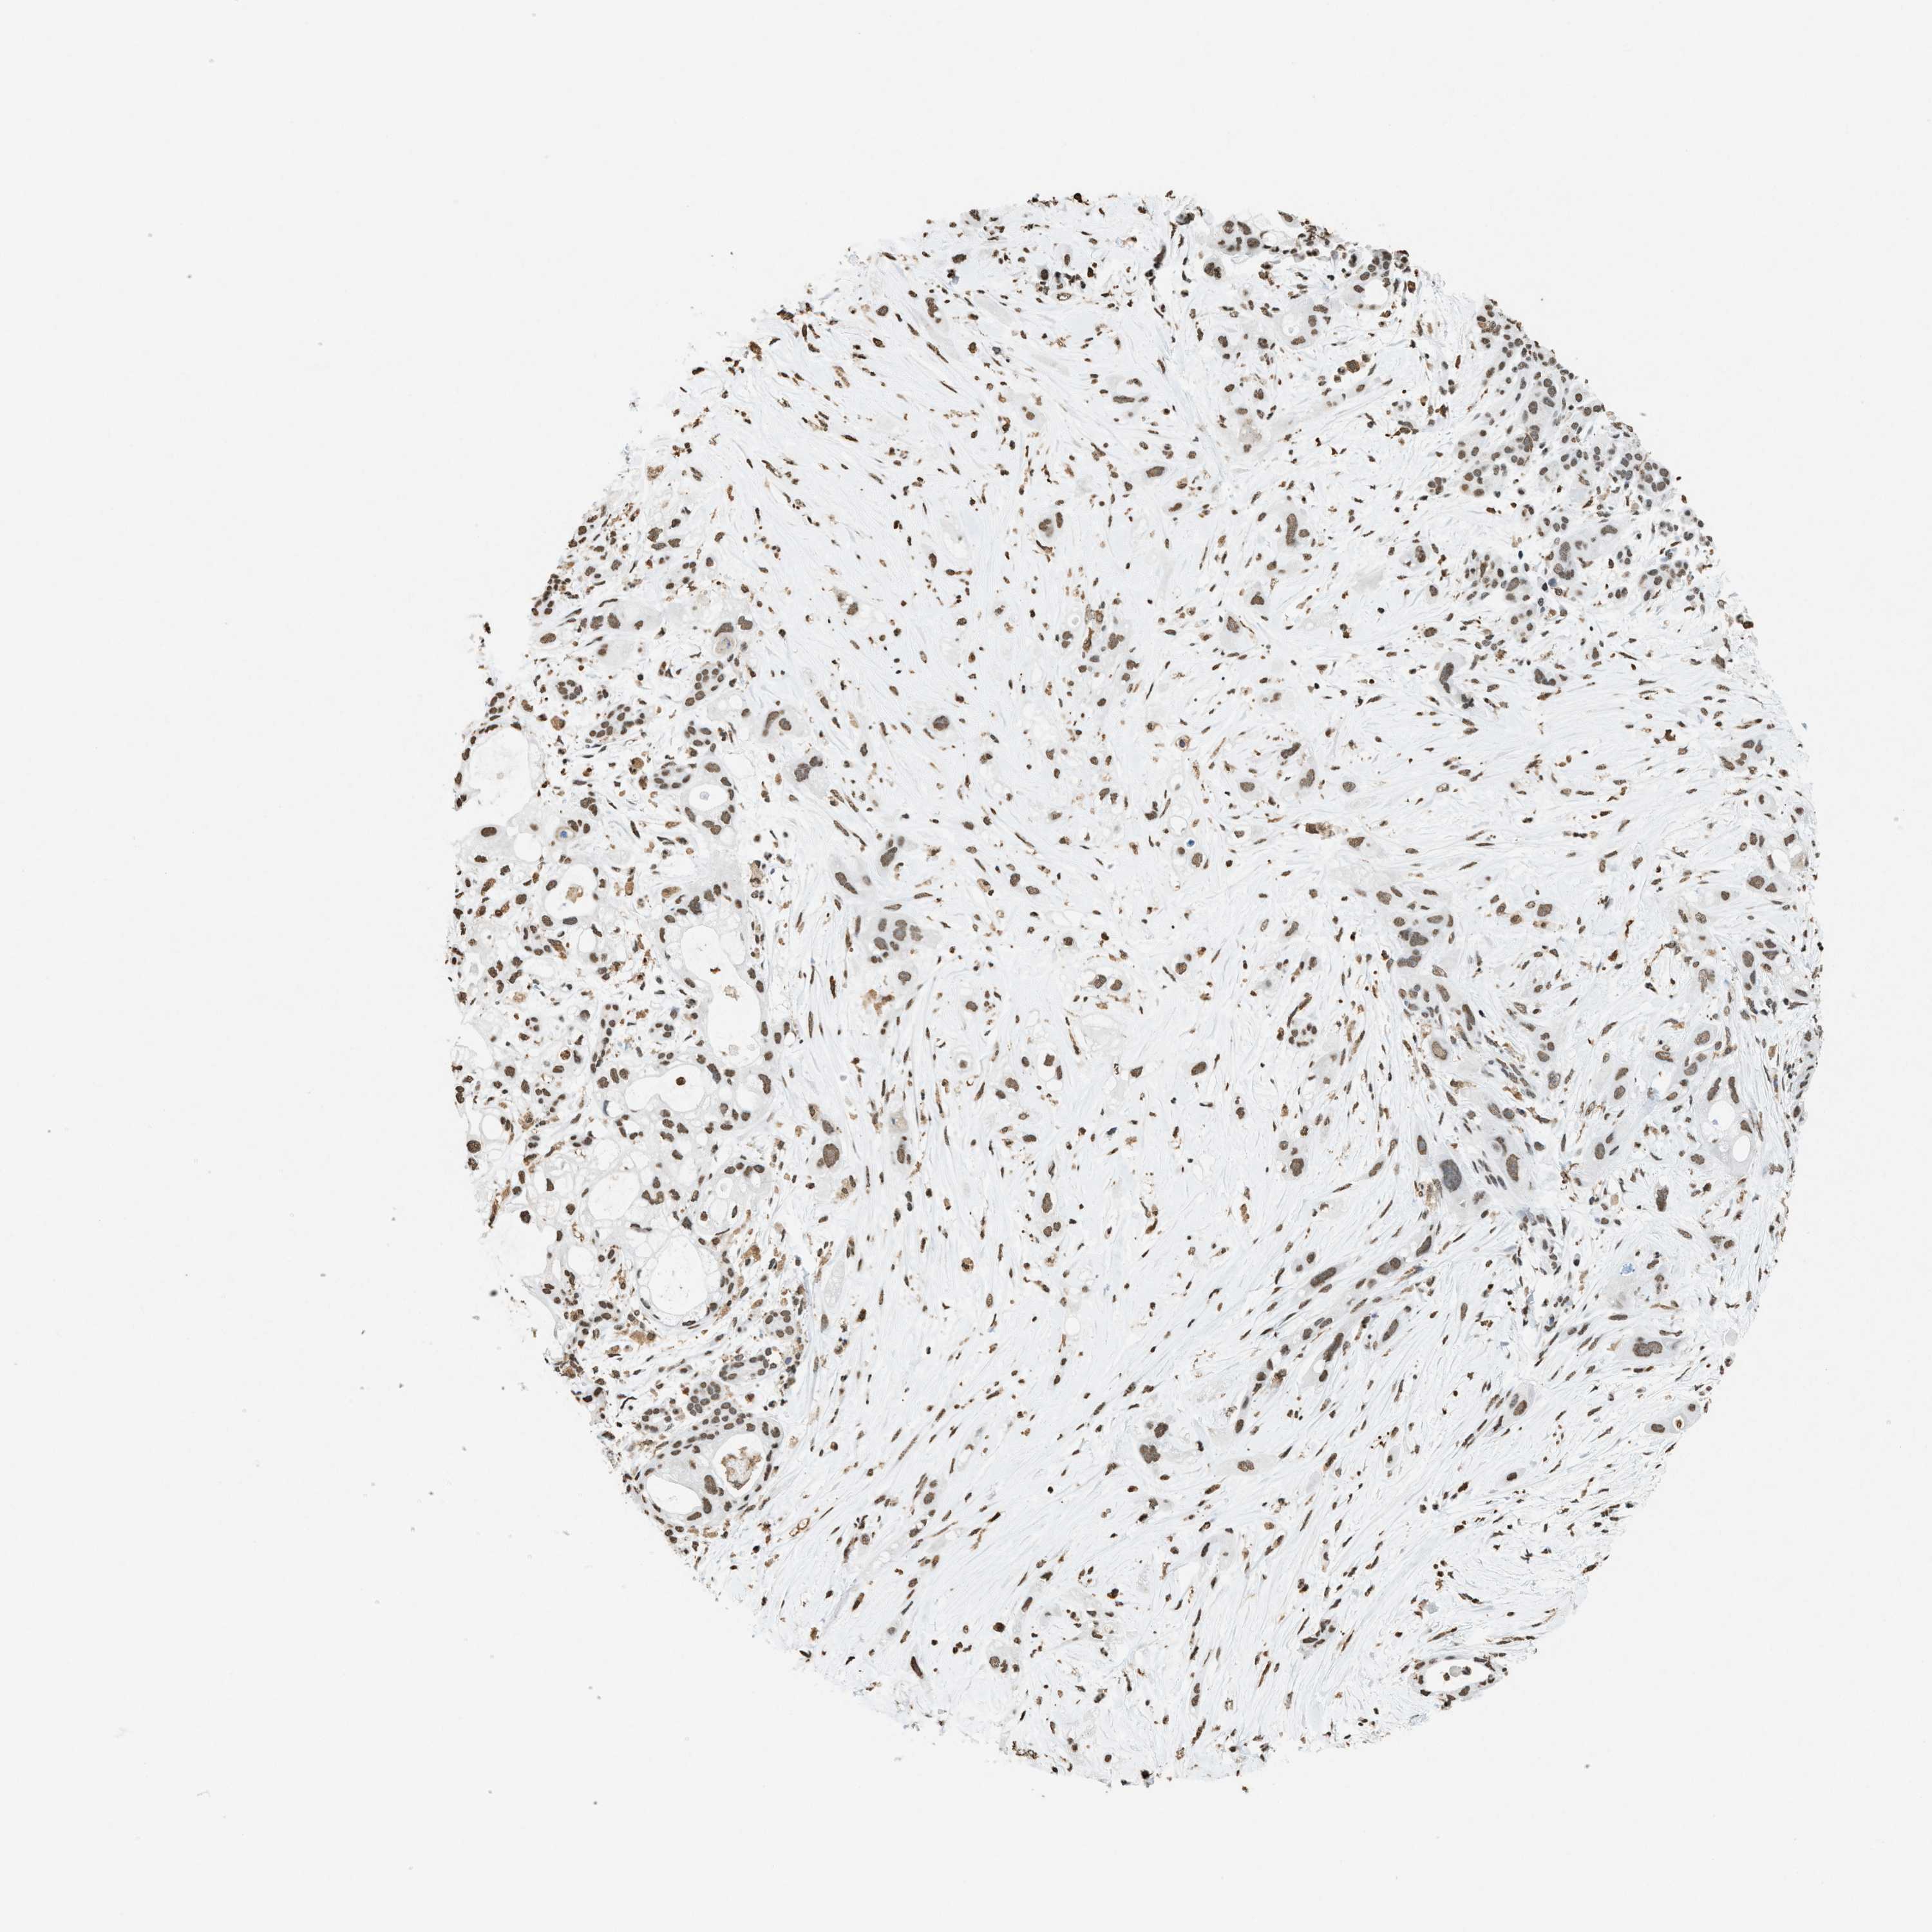

PANCREATIC CANCER - Protein expressioni

A mouse-over function shows sample information and annotation data. Click on an image to view it in a full screen mode. Samples can be filtered based on level of antibody staining by selecting one or several of the following categories: high, medium, low and not detected. The assay and annotation is described here.

Note that samples used for immunohistochemistry by the Human Protein Atlas do not correspond to samples in the TCGA dataset.

Antibody stainingi

Antibody staining in the annotated cell types in the current human tissue is reported as not detected, low, medium, or high, based on conventional immunohistochemistry profiling in selected tissues. This score is based on the combination of the staining intensity and fraction of stained cells.

Each image is clickable and will lead to virtual microscopy that enables deeper exploration of all samples and also displays staining intensity scores, fraction scores and subcellular localization as well as patient and tissue information for each sample.

Antibody HPA021816

Antibody CAB002209

Staining

High

Medium

Low

Not detected

Intensity

Strong

Moderate

Weak

Negative

Quantity

>75%

75%-25%

<25%

None

Location

Nuclear

Cytoplasmic/membranous

Cytoplasmic/membranous,nuclear

Adenocarcinoma, NOS

Adenocarcinoma, metastatic, NOS